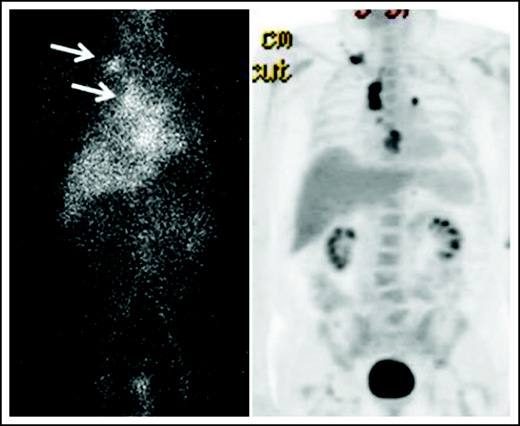

Biodistribution of 111In-basiliximab/DOTA at 144 hours in UPN-1 (left) and 18F-FDG-PET (right).